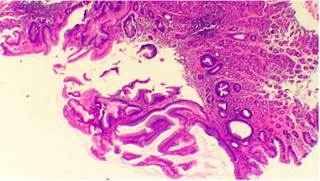

El estudio histopatológico reportó una mucosa esofágica comprometida por una lesión displásica, conformada por glándulas tubulares y vellosas, revestida por un epitelio cilíndrico simple, núcleos hipercromáticos sin evidencia de pérdida de la polaridad ni compromiso de la membrana basal. En la lámina propia se observó un infiltrado inflamatorio crónico en escasa cantidad, compatible con adenoma velloso, con displasia de bajo grado (Figuras 4 y 5).